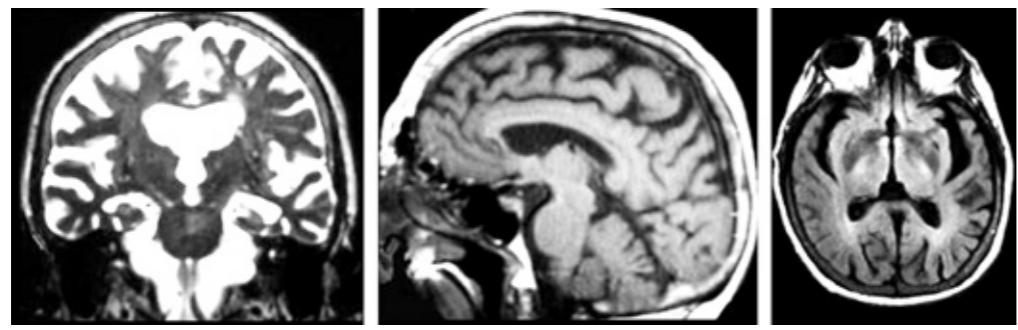

Asimismo, los pacientes que presentan enfermedad de Alzheimer muestran una atrofia cerebral que comienza en los hipocampos y amígdalas. Después, en lóbulos frontales y temporales. Con el avance de la enfermedad, todo el cerebro queda perjudicado. Así, tales daños concuerdan con el avance de la sintomatología de dicha afección.